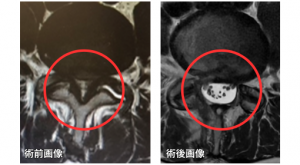

赤枠部分が脊柱管と呼ばれる神経が通る場所です。

術前(左図)ではかなり狭くなっていますが、

術後(右図)では広がって内部の神経や髄液が確認できます。